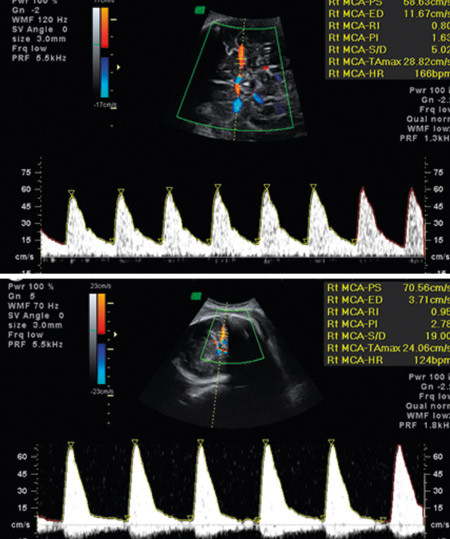

Den hyppigste blodtypeimmuniseringen hos gravide skjer mot antigenet Rh(D), oftest i tilslutning til forløsningen (fig 2). Det er blant medisinens store triumfer at det er blitt mulig å forebygge flertallet av disse immuniseringene samt forutsi og diagnostisere føtal anemi med ikke-invasive teknikker (1) (fig 3) og behandle anemiske fostre med intrauterine transfusjoner styrt med ultralyd. Profylaksen består i at den Rh(D)-negative kvinnen får injisert 1 250–1 500 IU IgG anti-D intramuskulært innen 72 timer etter forløsning (vaginal eller keisersnitt) av Rh(D)-positivt barn, samt ved amniocentese, morkakebiopsi, antepartumblødning, traume mot abdomen, ytre vending, intrauterin fosterdød, spontan eller provosert abort og ved operasjon for ekstrauterint svangerskap. Hvordan anti-D virker, er fortsatt ikke fullgodt forklart, men effekten er slående. Statistikk fra tidligere Helseregion 2 (Øst- og Vestfold, Buskerud, Telemark, Aust- og Vest-Agder) samt Oslo viser at det før 1970 var 300–350 nye Rh(D)-immuniseringer blant gravide i Norge per år. Etter at profylaksen ble innført i 1969, sank tallet raskt og var trolig 50–60 per år 1985 (2).

Figur 3  Dopplerundersøkelse av blodstrømshastighet i a. cerebri media ved uke 32 fra normalt foster (øverst) og anemisk…

Figur 3 Dopplerundersøkelse av blodstrømshastighet i a. cerebri media ved uke 32 fra normalt foster (øverst) og anemisk foster (nederst), med forhøyet systolisk maksimal strømningshastighet (> 1,5 g median verdi i forhold til svangerskapsalder)

Mot andre blodtypeimmuniseringer finnes det ikke profylakse. Alle gravide med klinisk betydningsfulle antistoffer trenger utredning og oppfølging for å identifisere fostre med risiko for å utvikle anemi. Det innebærer utredning av fosterets Rh-status ved hjelp av blodprøve av mor og gjentatte ultralydundersøkelser som inkluderer dopplermålinger (fig 3). Slik følges en ev. utvikling av fosteranemi, og man kan finne det gunstigste tidspunktet for ultralydveiledet intrauterin transfusjon. I postnatalperioden omfatter behandlingsmulighetene lysbehandling, immunmodulering med høydose intravenøst gammaglobulin og utskiftingstransfusjon. Tilgjengelig statistikk tilsier at det oppdages 50–60 nyimmuniseringer mot andre blodtypeantigener enn Rh(D) hos gravide per år (2). I tillegg kommer tilfeller av hemolytisk sykdom der mor har blodtype O og barnet blodtype A eller B og mors preformerte IgG anti-A eller anti-B gir hemolyse postnatalt (ABO-uforlikelighet).